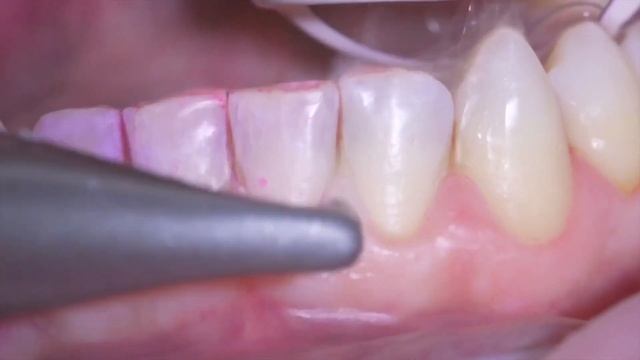

Airflow® and how to reduce aerosols смотреть онлайн

02:47

Airflow® and how to reduce aerosols

Числовой Чародей 32 просмотров